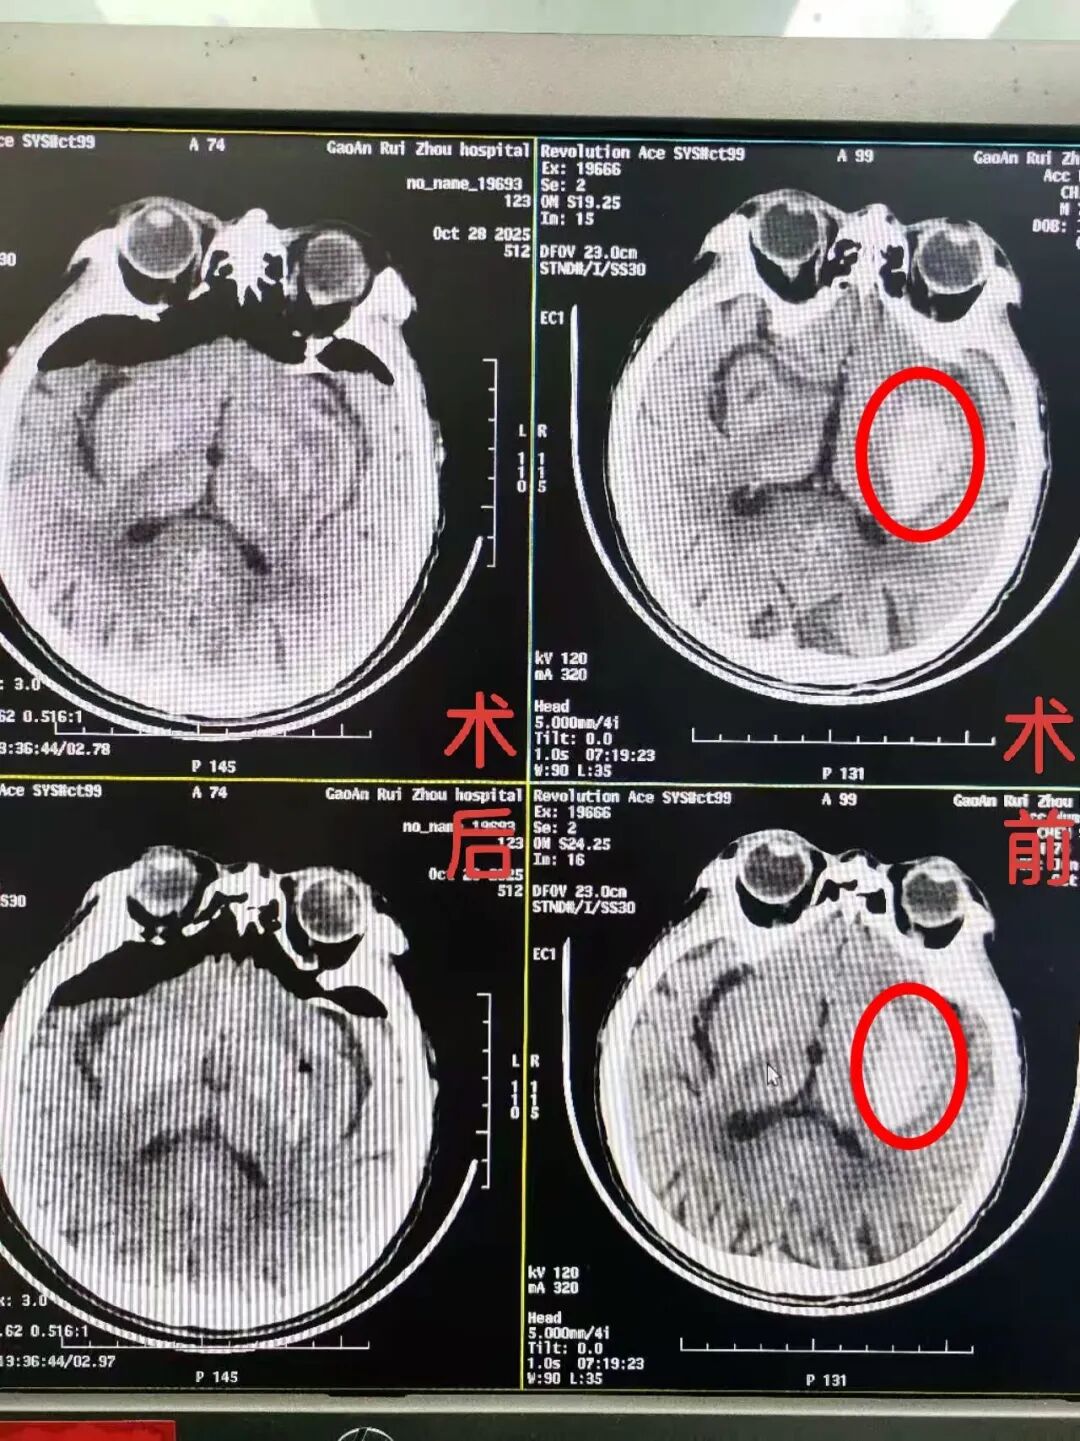

患者于2小时前无明显诱因突发意识不清(呼之能应,呈嗜睡状态),伴右侧肢体无力等症状。家属紧急送医后,急诊科立即启动卒中绿色通道,快速完成颅脑CT检查,结果明确显示“左侧基底节区脑出血”。病情危急,需立即住院治疗。

术中在颅内镜操作技术下,精准实施颅内血肿清除术,整个过程有条不紊、顺利完成。术后患者生命体征平稳,安返ICU严密监护。